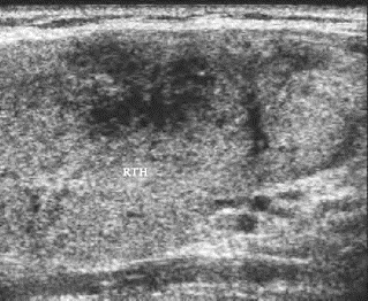

2.亚急性甲状腺炎超声表现(图7-6) 甲状腺单侧或双侧肿大,局部有压痛,甲状腺内可见单侧或双侧低回声,边界模糊,形态不规则,低回声内可见残存正常甲状腺点状回声,占位效应不明显,后方一般无衰减。

图7-6 亚急性甲状腺炎声像图

甲状腺右叶肿大,内部模糊的低回声